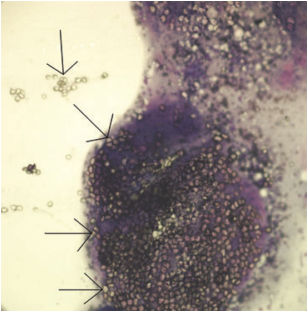

Fine-needle aspirate of a mesenteric lymph node from a dog. Dx? Describe.

Dx: Mesocestoides tetrathyridium infection

Hundreds of clear, refractile, calcareous corpuscles (arrows) from a ruptured cestode larva.

Cestode infection in 2 dogs: cytologic findings in liver and a mesenteric lymph node. Vet Clin Pathol 42/1 (2013) 103–108.